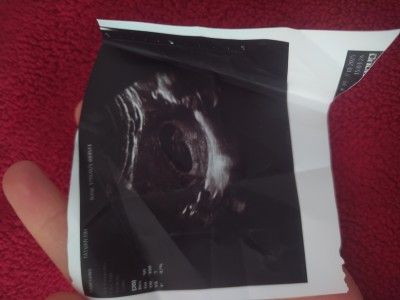

meraba kızlar cinsiyet tahmini yapabiliyor musunuz çok heyecanlıyım

Gebelik haftası 9 hafata

Kese şekli kıza benziyor cnm rabbim gönlüne göre versin

Ne kadar doğru bilmiyorum fakat kese düzgün bir yuvarlak ise kız, biraz uzun ise erkek derler hayırlı sağlıklı evlat olsun da sanki erkek gibi hissettim 🙂🙂